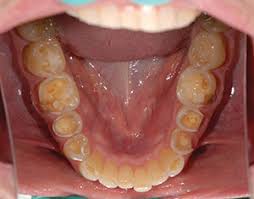

🛑Clinical presentation –

- Appearance of small polished facet on the cusp tip /ridge or slight flattening of the incisal edge

- Tooth discoloration : attrition and erosion of the enamel exposes inner and darker dentine giving a yellower appearance

- Altered occlusion due to decreasing occlusal vertical dimension